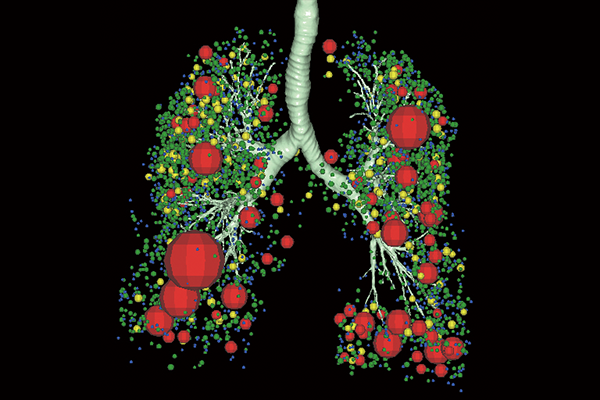

SYNAPSE 3D’s advanced image analysis technology aids clinical interpretation, reporting, and treatment planning. Especially, automatic organ segmentation technology enables fast and effective workflow, powered by REiLI, FUJIFILM's AI brand. With a series of high-tech applications developed in collaboration with clinical specialists, SYNAPSE 3D quickly and accurately delivers imaging result that promotes effective care collaboration.

REiLI makes it happen to extract organs and simplify your work.

Lung Analysis